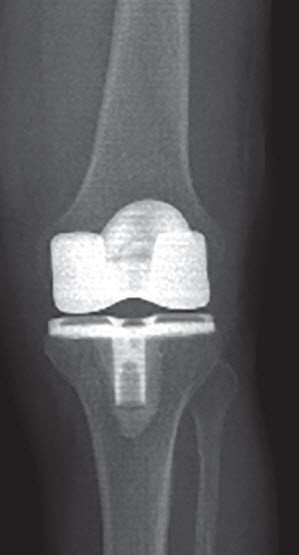

Medical condition Knee prosthesis – the artificial knee joint

An artificial knee joint is used to replace the natural sliding and surface areas of the knee joint when these have become worn.

The components for replacing these surfaces, the femoral cap and the tibial plate, are made from highly polished metal (cobalt-chromium alloy). Between the metal surfaces there is a cartilage replacement made from polyethylene (a highly advanced plastic). Once the components of the artificial knee joint have been implanted in the body, they are held together in a stable position and guided during movement by the knee’s own ligaments, the joint capsule and the strength of the muscles.

Special bone cement is generally used to attach the metal surfaces to the bone. If the bone is of very high quality, a knee prosthesis can also be implanted without using cement. When attaching the metal to the bone without using cement, the back of the metal components is covered with a special surface which allows for the ingrowth of bone cells.